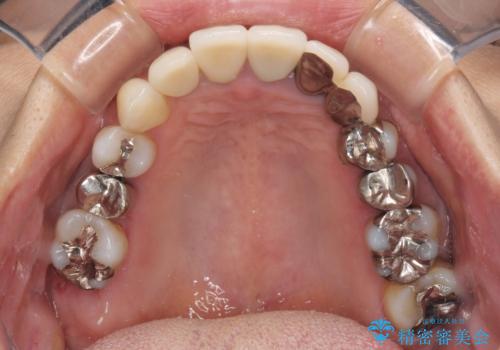

- 歯を磨く度に奥歯から出血するとのことで来院された患者様です。

歯周ポケット検査を行ったところ、6-8mmの歯周ポケットが散見され(正常では3mm以下)、歯周病治療が必要と判断されました。

仮歯に置き替え、歯周外科処置(APF、歯肉弁根尖側移動術)による歯周ポケット除去を行った後に、オールセラミッククラウンにて補綴することとしました。

歯周外科処置により歯周ポケットを除去することができ、クラウン装着後はブラッシング時の出血や歯肉の腫れが気にならなくなりました。